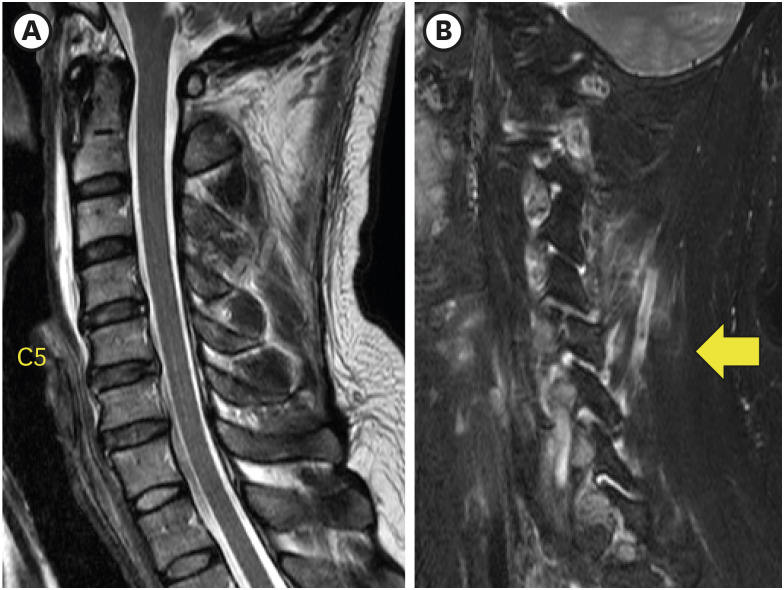

一名 42 岁男子从树上摔下后出现颈部疼痛。脊柱计算机断层扫描(CT)显示右侧 C5 上关节突骨折,无移位。磁共振成像(MRI)证实了骨折和后韧带复合体损伤。起初,由于没有不稳定或椎体错位的迹象,他接受了颈部支撑的保守治疗。然而,出院三天后,右肩无力和右上臂麻木的症状开始突出。X光片和CT显示,C4椎体前滑,C4/5椎面锁定,C5上关节突骨折骨片被锁定的C4下关节突推向前方,侵入神经孔。采用同种异体移植和钢板/螺钉固定,进行了颈椎前路椎间盘切除和融合术(ACDF)。虽然最初的影像学检查未显示有脱位迹象,但外科医生应注意隐匿性不稳定性以及与单侧颈椎面骨折相关的延迟脱位的可能性。

A 42-year-old man presented with neck pain after a fall from a tree. Spine computed tomography (CT) illustrated the right C5 superior articular process fracture without displacement. Magnetic resonance imaging (MRI) confirmed the fracture and injury of the posterior ligament complex. Initially he was managed conservatively with a neck brace as there were no signs of instability or vertebral body misalignment. However, three days after discharge, right shoulder weakness and numbness of the right upper arm became prominent. X-rays and CT showed anterior slippage of the C4 vertebral body and locked C4/5 facet ??a fractured bony fragment of the C5 superior articular process was pushed forward by the locked inferior articular process of C4 and invaded the neural foramen. Anterior cervical discectomy and fusion (ACDF) was performed using allograft and plate/screws fixation. Although initial imaging showed no evidence of subluxation, surgeons should be aware of occult instability and the possibility of delayed dislocation associated with the unilateral cervical facet fracture.